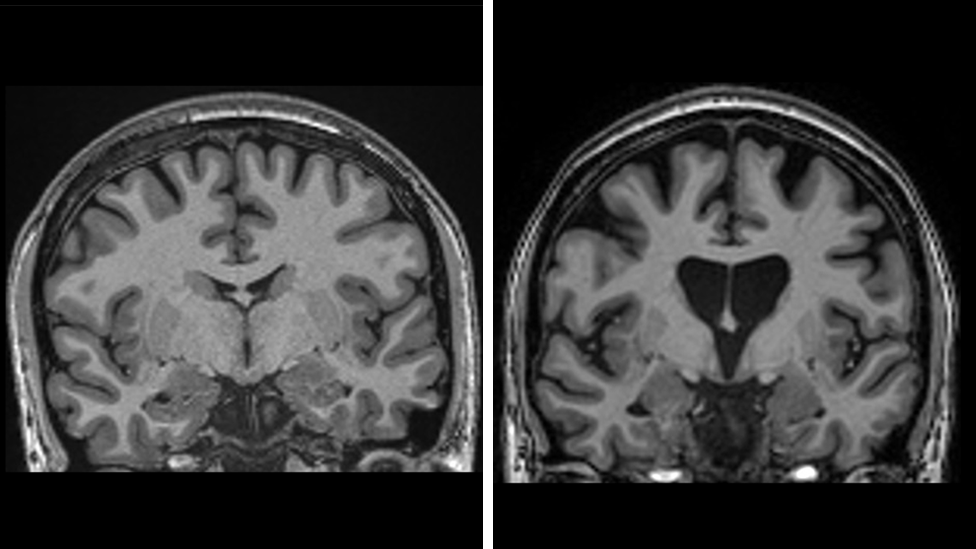

Ovim tretmanom se štede moždane ćelije, ukazuje ispitivanje.

Ako bolest napreduje onda se nivo neurofilamenata (elementi koji ukazuju da umiru moždane ćelije) u kičmenoj tečnosti povećava za trećinu, ali su zapravo bili niži u odnosu na parametre pre početka ispitivanja.

To ukazalo da je došlo do usporavanja razvoja bolesti.